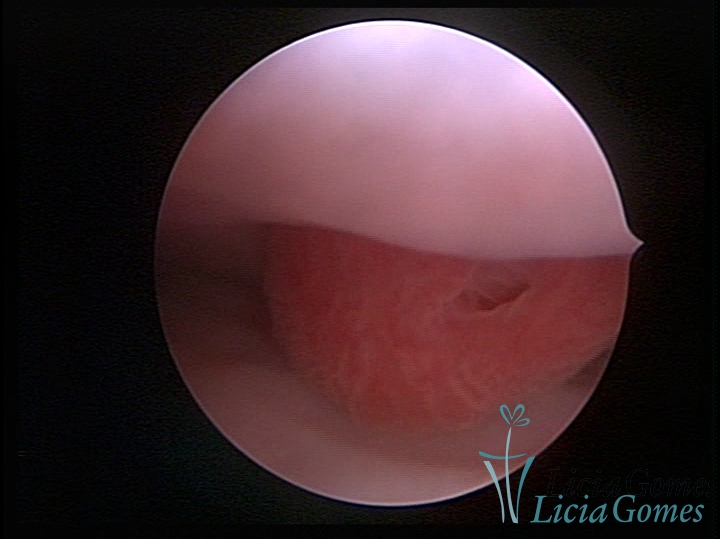

PÓLIPOS ENDOCERVICAIS

São tumores benignos, resultantes da proliferação focal reativa aos processos inflamatórios ou à situações de hiperestrogenismo, e podem ter sésseis (com a base de implantação larga) ou pediculados do epitélio.